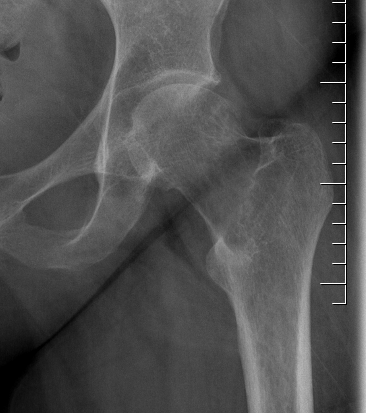

X-ray

Eccentric, sharply demarcated lytic lesion

- no sclerosis around lesion

- narrow zone of transition

- metaphysis, extending into epiphysis

- no mineralization

CT

Imaging

Grade III with cortical destruction and soft tissue extension